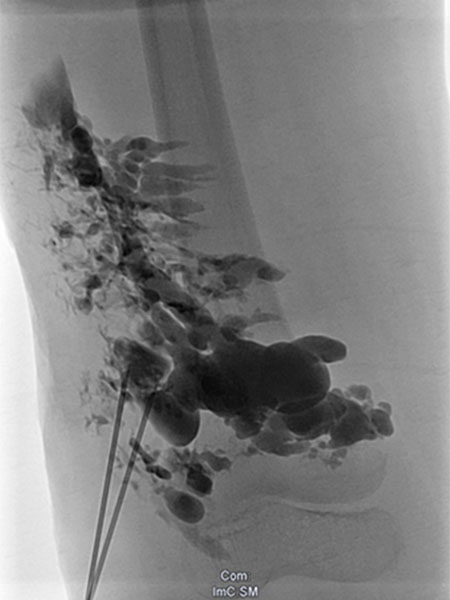

Lymphography with contrast injection directly into the lymphatic malformation subcutaneously, underneath the capillary malformation laterally on the thigh which is visible on the skin. The entire lymphatic malformation is contrasted from this needle position. Thus the ideal position for sclerosing this portion.

Re-puncture and lymphography with contrast injection will contrast additional parts of the lymphatic malformation, which can then be sclerosed.

Injection of sclerosant (in this case picibanil = OK-432), which is in itself non-contrasting, displaces the previously injected contrast. In this way, the entire lymphatic malformation is sclerosed in successive steps. This results in sealing of the skin and decreases future lymphorrhea. The marginal vein is additionally occluded by radiofrequency ablation (not shown) to prevent thromboembolism.